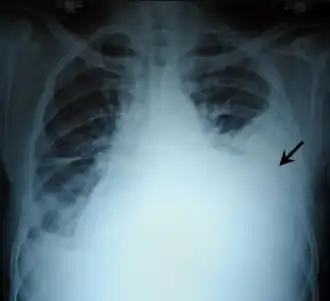

![]() Radiografía de tórax con un hemotórax izquierdo (flecha negra) | ||